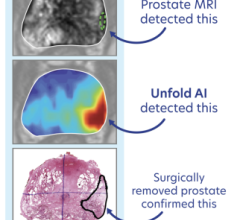

In the joint research project, the Netherlands Cancer Institute, University of Twente and industry partners Lightpoint Medical and Philips will evaluate a novel molecular imaging technology to image the prostate cancer biomarker prostate specific membrane antigen (PSMA) during surgery. If successful, the technology will be tested in larger clinical trials, with the aim of sparing healthy tissue and reducing recurrence rates in prostate cancer surgery.

Marcel Stokkel, M.D., nuclear medicine physician at NKI, commented, “If this technique is successful, we will be able to guide the urologist in the most optimal way by combining pre-operative staging with per-operative imaging using the same tracer. If the resection margins can be assessed with highest accuracy during surgery, we might become able to improve recurrence and survival rates. The collaboration with Lightpoint Medical, Philips and the University of Twente is the most optimal setting to reach this goal and to complete this study.”